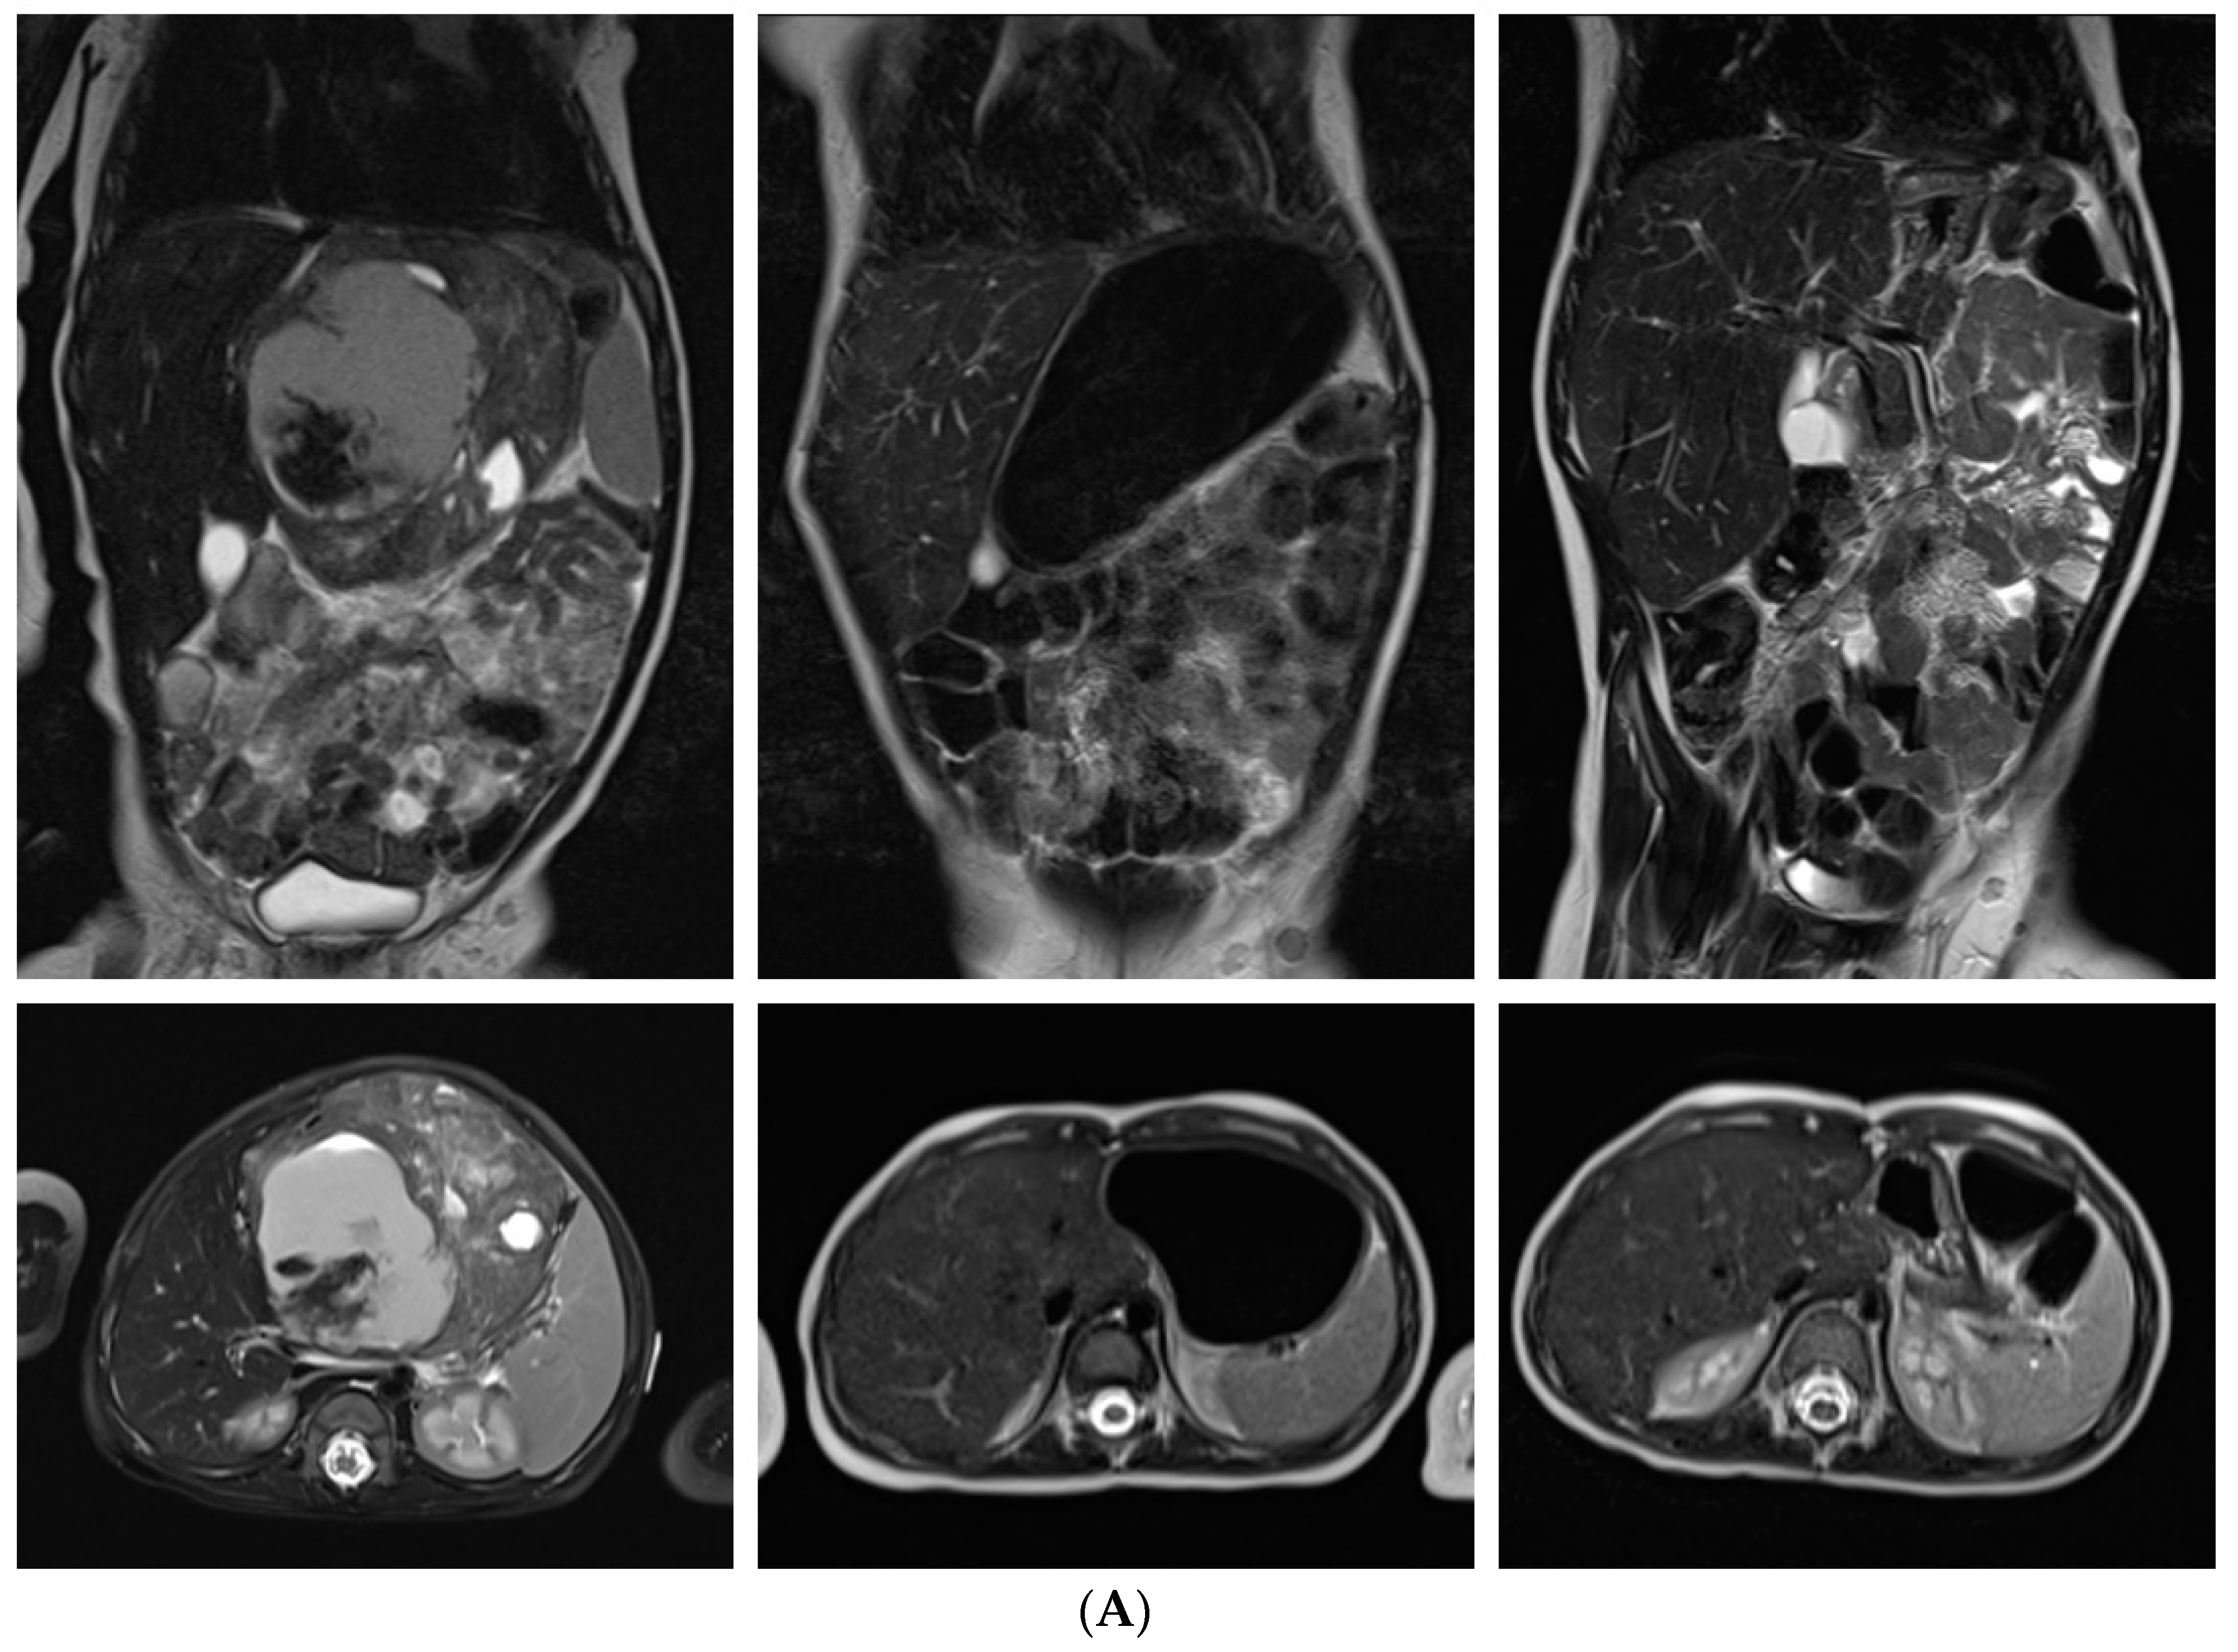

| Extracranial MRT | 55 |

| Liver | 7 |